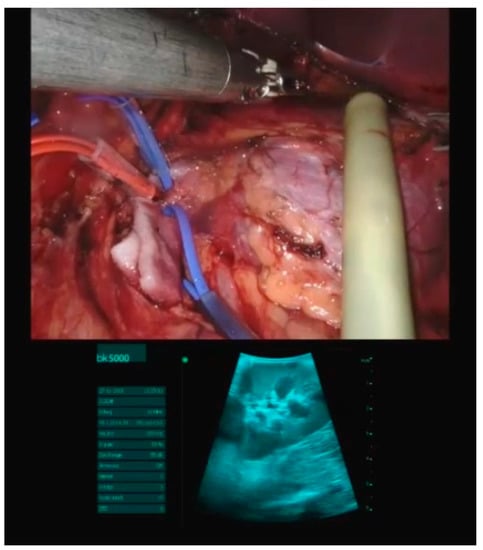

6. Intraoperative Ultrasonography and Robotic-Assisted Surgery

- Zhu, P.; Liao, W.; Ding, Z.-Y.; Luo, H.-C.; Zhang, B.-H.; Zhang, W.-G.; Zhang, W.; Zhang, Z.-G.; Zhang, B.-X.; Chen, X.-P. Intraoperative ultrasonography of robot-assisted laparoscopic hepatectomy: Initial experiences from 110 consecutive cases. Surg. Endosc. 2018, 32, 4071–4077. [Google Scholar] [CrossRef]

- Li, Q.; Li, N.; Luo, Y.; Yu, H.; Ma, X.; Zhang, X.; Tang, J. Role of intraoperative ultrasound in robotic-assisted radical nephrectomy with inferior vena cava thrombectomy in renal cell carcinoma. World J. Urol. 2020, 38, 3191–3198. [Google Scholar] [CrossRef]